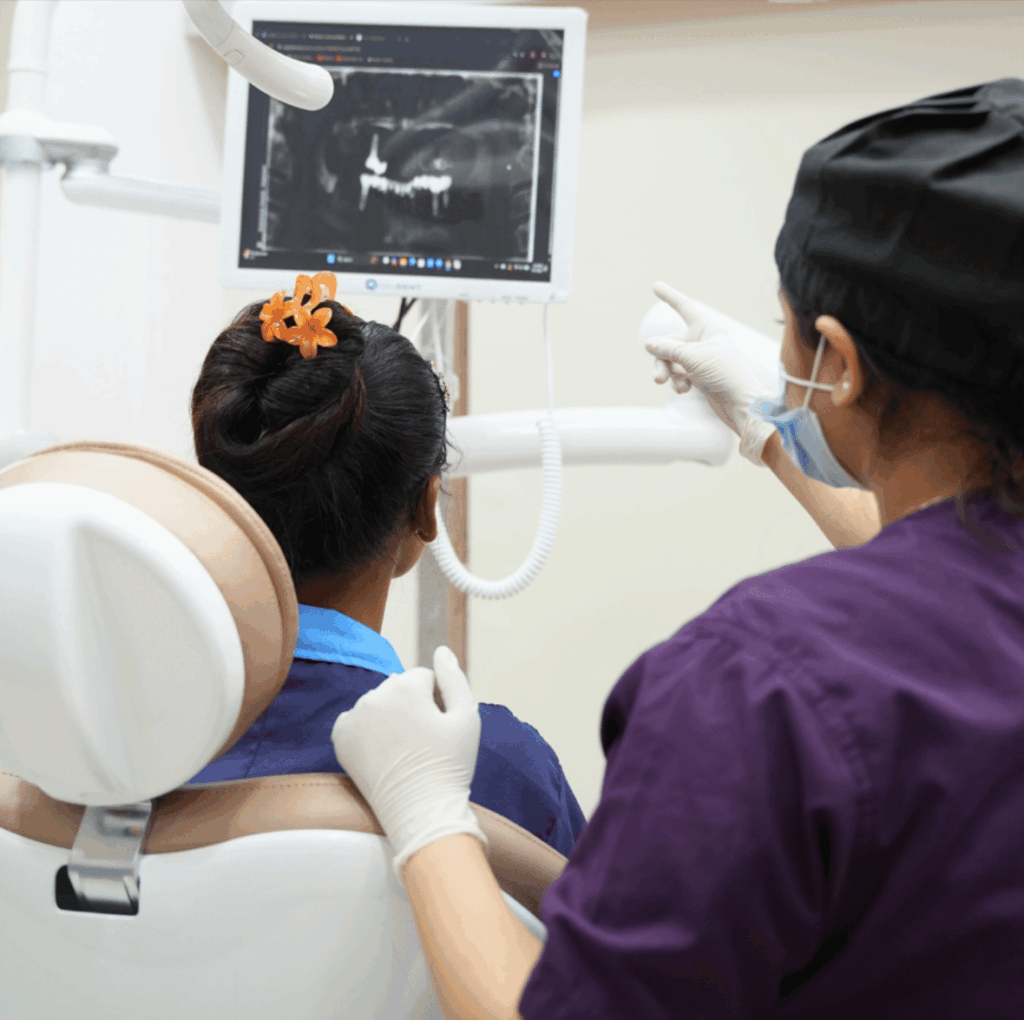

At Summirow Dental Care Hospital, we believe a strong smile builds strong confidence. If you have a damaged, weak, or missing tooth, our advanced Dental Crowns and Bridges in Surat are designed to restore both function and aesthetics, seamlessly and comfortably.

A Dental Crown is a custom-designed cap that completely covers and protects a damaged or weakened tooth, restoring its strength, shape, size, appearance, and proper bite function.

The affected tooth or supporting teeth are gently shaped to prepare for the crown or bridge placement.

Your crown or bridge is permanently placed using high-quality dental cement, followed by bite and comfort checks.